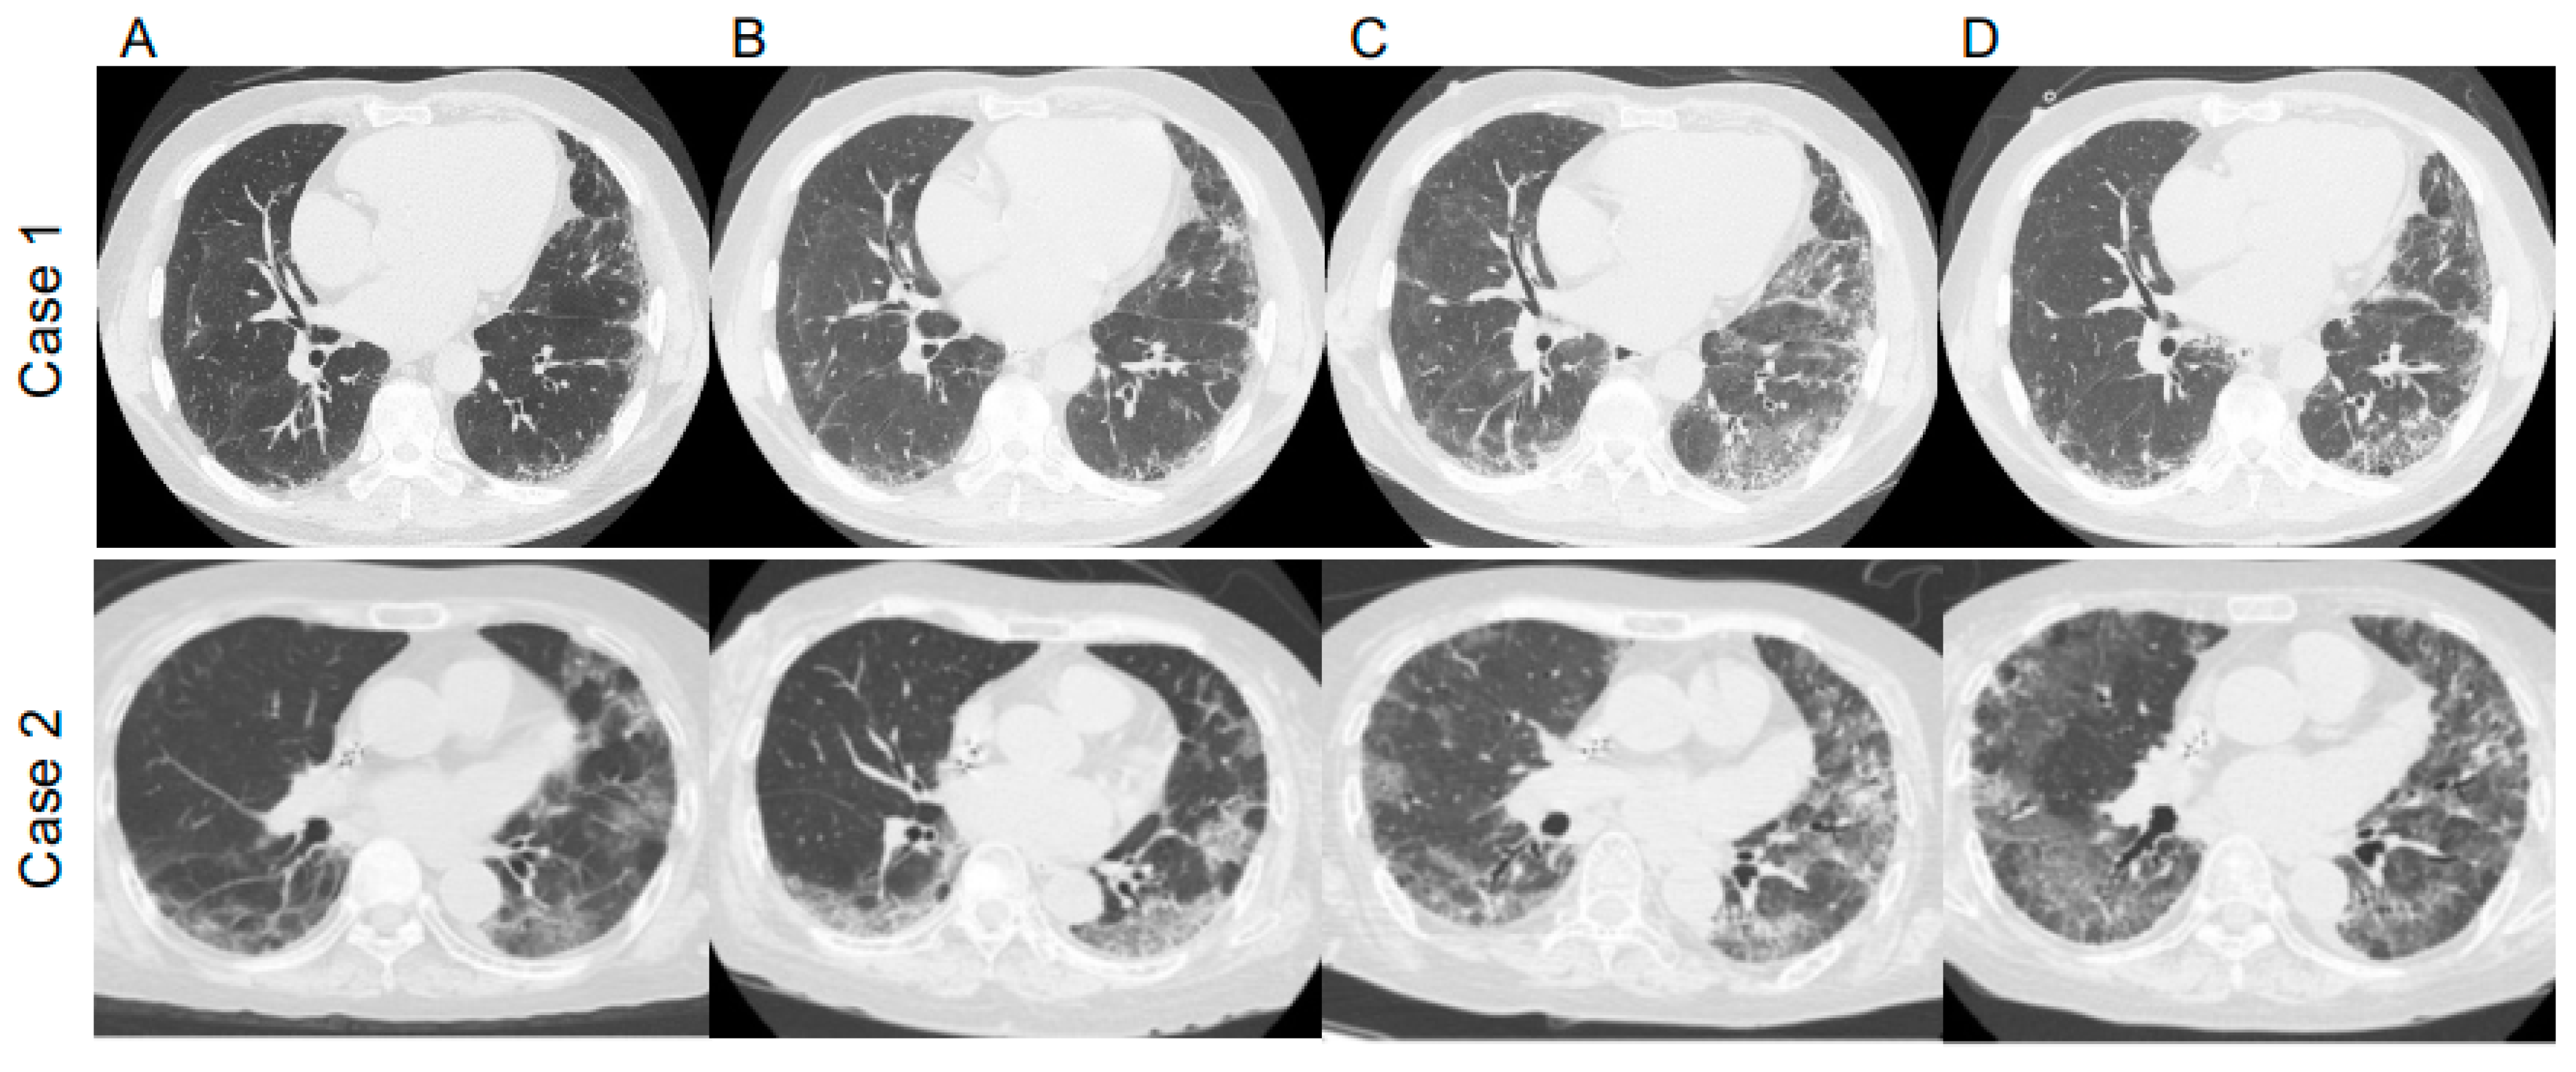

Figure 2.

Chest computed tomography (CT) images of Case 1 and Case 2 (A) at COVID-19 diagnosis, (B) after treatment of COVID-19, (C) at Pneumocystis jirovecii pneumonia (PJP) diagnosis, and (D) after PJP treatment with trimethoprim–sulfamethoxazole.

A 69-year-old man diagnosed with IP in 2018 and receiving oral prednisolone (PSL) at a maintenance dose of 10 mg daily developed a fever in April 2020, and the polymerase chain reaction (PCR) test was positive for SARS-CoV2. He had not received the COVID-19 vaccine. Treatment began with oral favipiravir, which was widely used for COVID-19 treatment in Japan at the time. However, due to the patient’s lack of improvement and poor oxygenation, he was admitted to our hospital on the seventh day after his illness began. Upon examination, his body temperature was 36.2 °C, his heart rate was 51 beats/min, and his oxygen saturation was 94% (room air). The blood examination showed the following results: white blood cells (WBC) 30.1 × 103/μL, hemoglobin (Hb) 14.8 g/dL, platelets 45.8 × 104/μL, Na 136 mEq/L, K 4.2 mEq/L, Cl 97 mEq/L, C-reactive protein (CRP) 0.75 mg/dL, blood urea nitrogen (BUN) 23 mg/dL, creatinine (Cre) 0.88 mg/dL, aspartate aminotransferase (AST) 72 IU/L, alanine aminotransferase (ALT) 92 IU/L, and lactate dehydrogenase (LDH) 370 U/L. These findings are typical in the early stages of COVID-19 infection. Figure 1A depicts the patient’s clinical course. Ground-glass opacities and consolidation were seen on chest computed tomography (CT) (Figure 2). COVID-19 pneumonia was almost completely resolved after the fever subsided. The patient developed fever again on the 19th day after the onset of the disease (Day 19), and a chest CT scan revealed a new ground-glass opacity (GGO), thereby raising the possibility of pneumonia caused by a common bacterium. Levofloxacin treatment was ineffective, and an increase in serum β-D-glucan levels to 9.7 pg/mL increased the possibility of PJP. The fact that trimethoprim–sulfamethoxazole (TMP–SMZ) improved pneumonia led to a clinical diagnosis of PJP.

A 70-year-old woman taking 4 mg of PSL orally daily for IP and rheumatoid arthritis was admitted to our hospital in April 2021 for COVID-19 treatment for 18 days (Days 7–25), where dexamethasone and tocilizumab were used. She had not received the COVID-19 vaccine. She began coughing one week after discharge (day 33), and five days later, she developed respiratory failure, with a chest CT revealing worsening pneumonia. Therefore, she was readmitted to the hospital (Day 38). During the second examination, her body temperature was 36.3 °C, her heart rate was 91 beats/min, and her oxygen saturation was 94% (2 L/min). The blood examination showed the following results: WBC 11.0 × 103/μL, Hb 12.0 g/dL, platelets 14 × 104/μL, Na 123 mEq/L, K 4.5 mEq/L, Cl 90 mEq/L, CRP 16.24 mg/dL, BUN 16 mg/dL, Cre 0.57 mg/dL, AST 23 IU/L, ALT 12 IU/L, and LDH 438 U/L. At this time, the quantitative SARS-CoV-2 antigen test was negative. Figure 1B depicts the patient’s clinical course. Her respiratory failure worsened after admission, her serum CRP was elevated, and a chest CT revealed an enlarged GGO (Figure 2). Ultimately, the diagnosis of PJP was made on the basis of high serum β-D-glucan levels and positive PCR for P. jirovecii DNA in the sputum. Thus, she was given TMP–SMZ treatment, but her respiratory failure worsened and she died on Day 49. She was subjected to a pathological autopsy. The lungs were clogged, and the histological assessment revealed multiple diffuse vitreous membranes, a sign of diffuse alveolar damage (DAD). Her collagen fiber increased in the interstitium, and numerous fibroblast foci were found in the alveolar wall and space. Furthermore, there was mucinous and exudate accumulation in the interstitium and alveolar space (Figure 3). Additionally, P. jirovecii cyst was identified. Although COVID-19 pneumonia and acute exacerbation of IP could cause DAD, PJP was determined to be the cause based on clinical and laboratory findings.